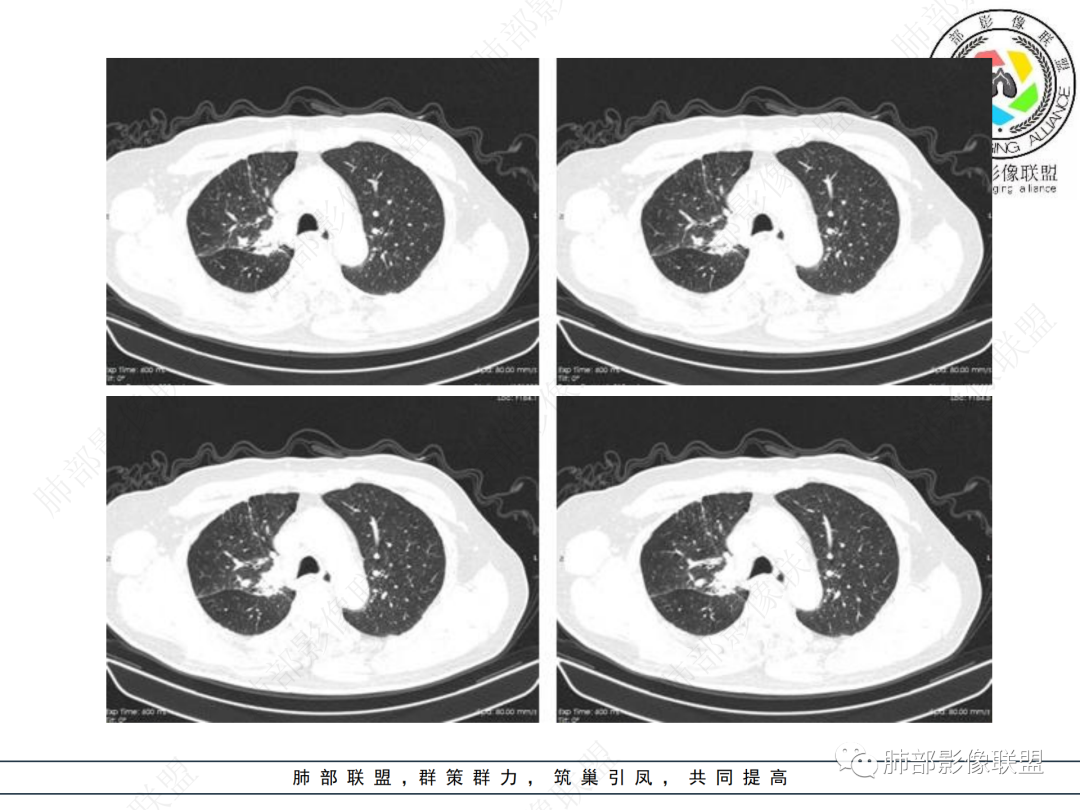

老年男性,病史2年,加重3天

提示慢性病史

加重3天——提示有急性病变,或原病变突然加重

右上胸廓较对侧慢性缩小

右上叶体积缩小

慢性病变有

内部支气管近端狭窄,远端粘液栓

结核要考虑下

内部血管也通畅

边缘也算平直

不踏实的是这里稍膨隆

恶性待排吧

结合本病例,老年男性患者,慢性病程,急性加重,无吸烟史,影像学表现为右肺上叶尖后段斑片实变密度影,整体边界清晰,边缘平直收缩为主,周边散在纤维条索影,内部见支气管内粘液栓,血管影走形正常,没有明显破坏,增强扫描明显强化,缺乏典型分叶毛刺、胸膜改变,病灶也未显示清楚的磨玻璃勾边,病灶大而肺门纵隔未见肿大淋巴结,综合考虑慢性炎性肉芽肿可能性大。但恶性,结核能完全排除吗?我想对临床医生来说还是有很大考验的。